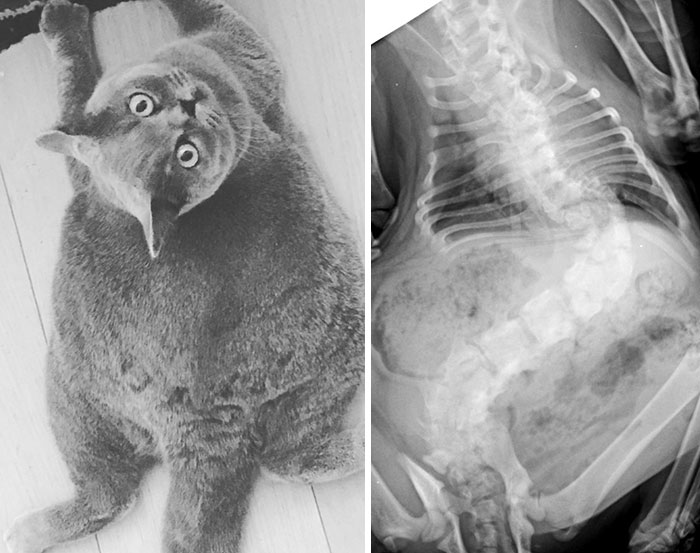

Pregnant Cat X-Ray

X-Ray Of A Pregnant Dog